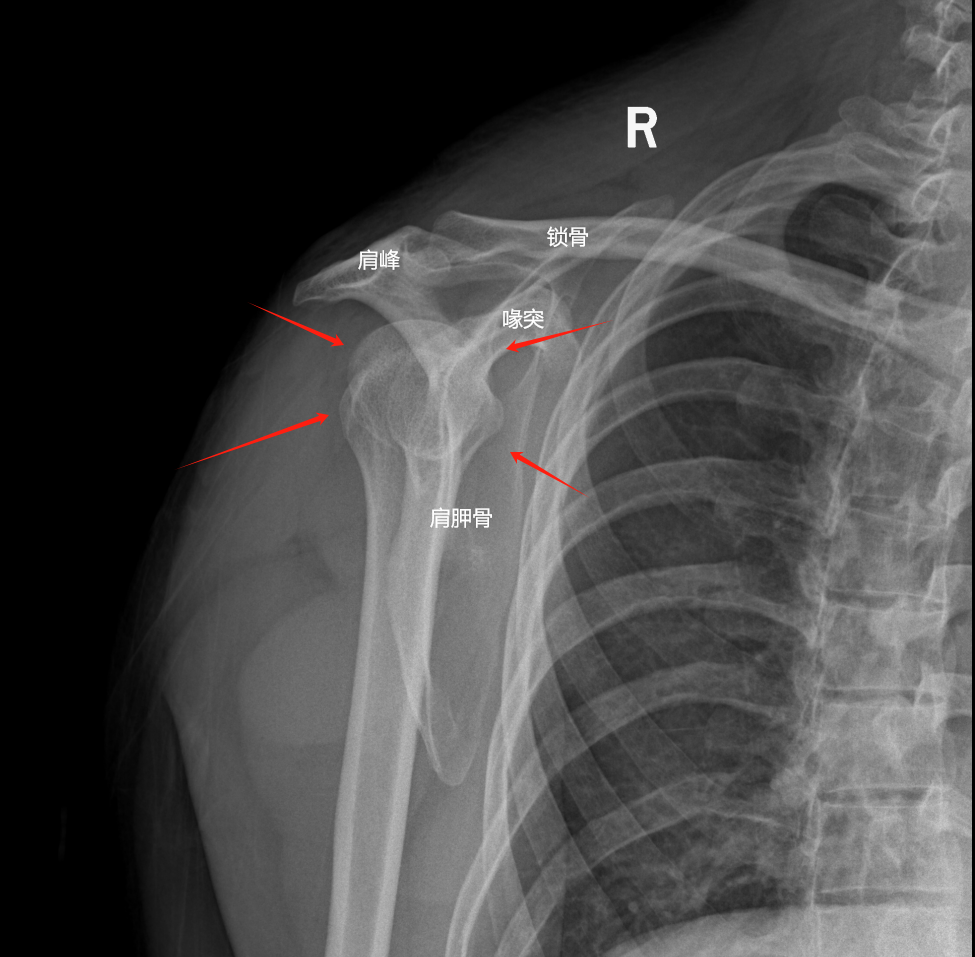

DR拍片可并非魔法,它靠的是X射线这一特殊“视线”。当它穿透你的身体时,不同组织吸收程度各异——致密的骨骼如同坚固壁垒,拦下大部分射线,在照片上便留下清晰白影;而柔软的肌肉组织则像薄纱,射线轻松穿过,呈现出深浅不一的灰黑影像。

于是,一张黑白分明的“骨骼高清自拍”便诞生了。医生们如同经验老道的侦探,在这张照片上搜寻蛛丝马迹:原本流畅的骨线条是否突然中断?是否出现了不该有的错位?是否能看到细微如发丝的裂缝?

火眼金睛  DR的高分辨率让骨骼细节无处遁形。即使细微如手腕处的“克雷氏骨折”或脚踝上的骨裂,也常能被它敏锐捕捉。清晰的影像为医生提供了坚实可靠的判断基础,避免误诊漏诊,让治疗精准起步。

明察秋毫  骨折之后,骨头是乖乖待在原位,还是已经“离家出走”?DR能清晰展现骨折断端的位置关系和移位程度。这份直观情报,直接决定着医生是采用温柔的“手法复位”,还是需请出“手术钢板”来重建秩序。